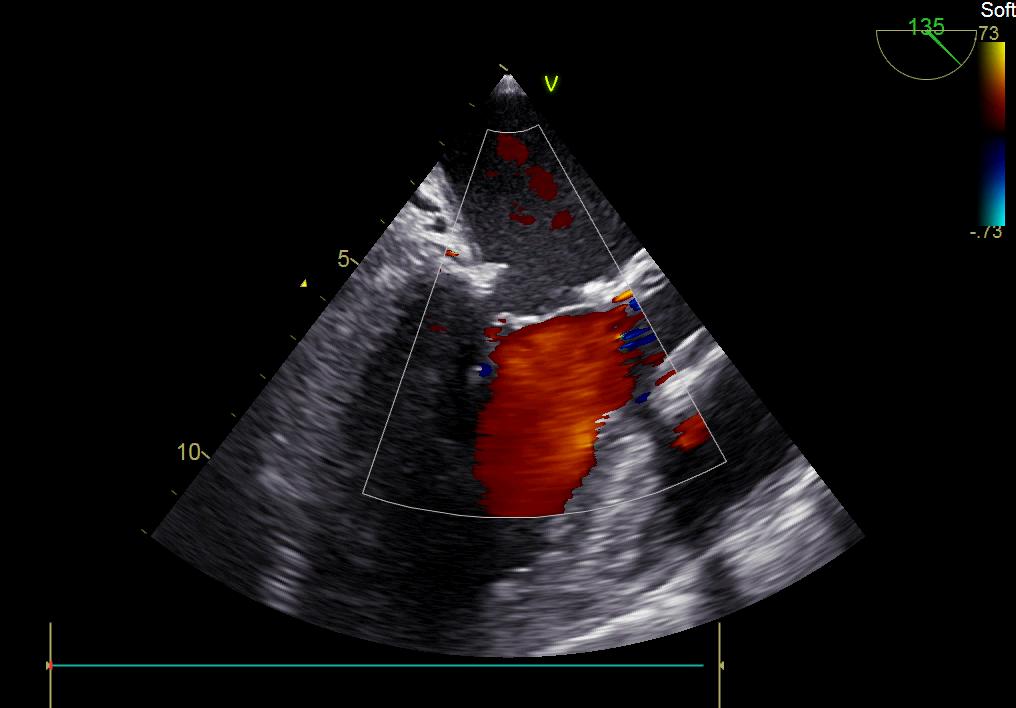

術(shù)后彩超